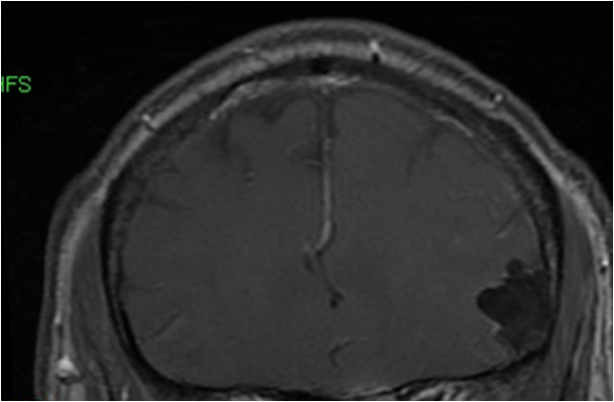

The Rock before it was taken into custody by the Mayo Clinic pathology team

Well, there it is. The Rock was the size of a golf ball and was described to me as “hard as a rock”.

Another look at Rock…

Get a good look at Rock…….his days are numbered. 6 to be exact!